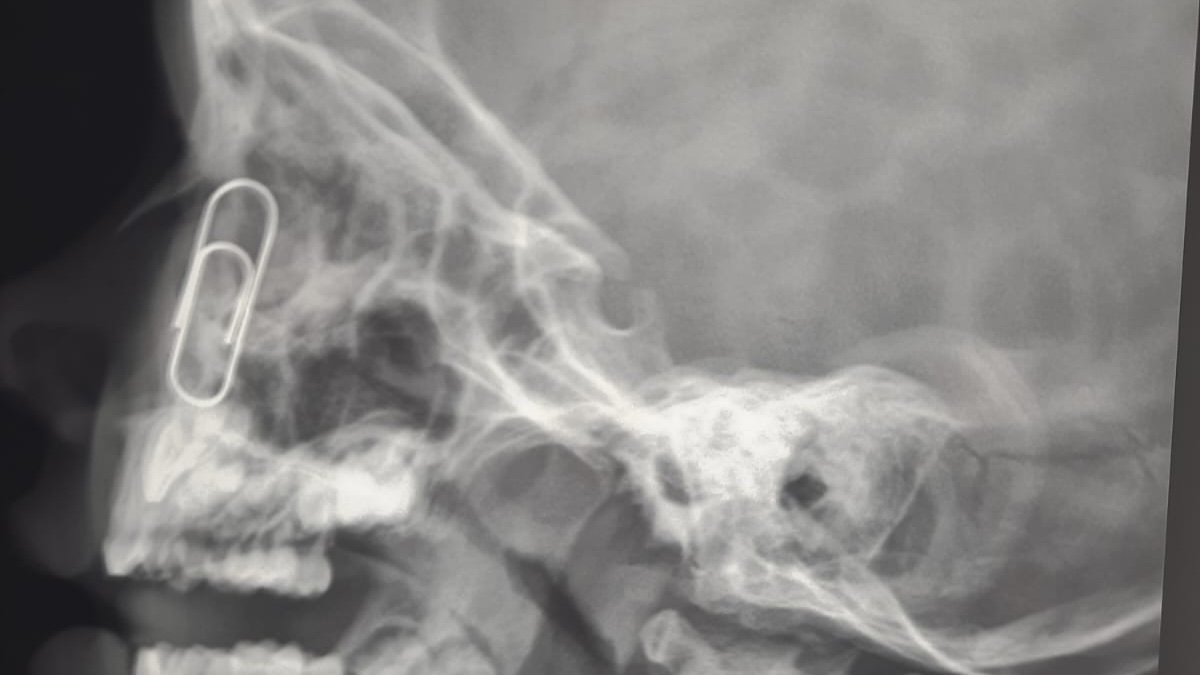

Владимирские врачи успешно удалили скрепку из носа 4-летнего малыша. Об этом сообщила пресс-служба ОДКБ в четверг, 11 сентября.